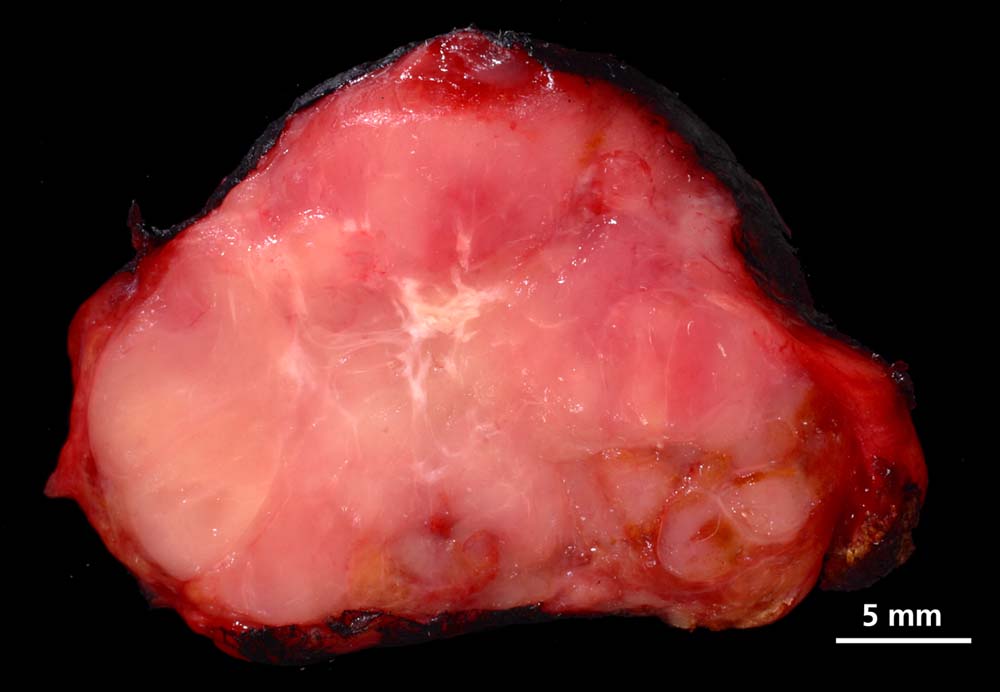

Die papillären Karzinome messen bei Diagnosestellung durchschnittlich 2.3cm und sind in bis zu drei Vierteln der Fälle multifokal. Makroskopisch sind die Tumoren blass, derb und unscharf begrenzt. Eine Kapsel liegt nur in 10% der Fälle vor. Papilläre Mikrokarzinome messen definitionsgemäss weniger als 1cm im Durchmesser und stellen häufige Zufallsbefunde in Strumektomien dar. Solche zufällig detektierten Mikrokarzinome haben bei Fehlen von histologischen Risikomerkmalen keinen Krankheitswert. Makroskopisch präsentieren sich Mikrokarzinome oft als grauweisse Narben.

Makroskopie

Befund

Pathologischer Befund